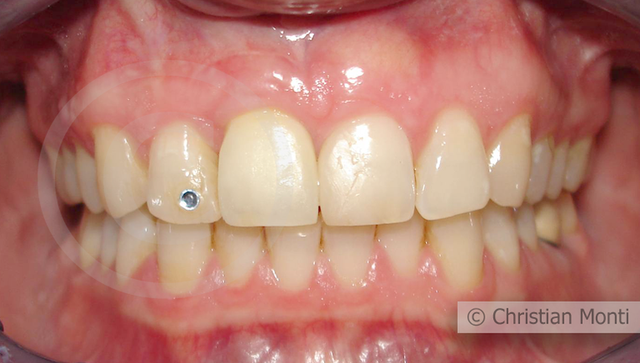

EDENTULIA SINGOLA

Impianto in sostituzione di un incisivo superiore